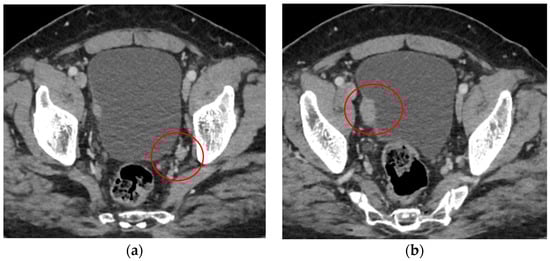

2. Case Report